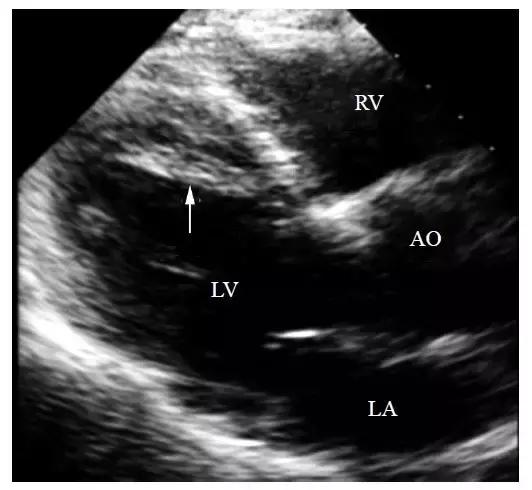

1.左心室腔可见到一条或数条索条状影(图1),回声较细,索条粗细不一,多在4 ~ 5mm以内,有一定活动度,随左心室舒张和收缩而紧张和松弛,追踪其附着点一端常位于室间隔上段,另一端位于左心室前壁、侧壁或心尖区。其特点是不与乳头肌和二尖瓣叶相连。

图1 左心室假腱索(箭头所指)

(AO-主动脉 LA-左心房 LV-左心室 RV-右心室)